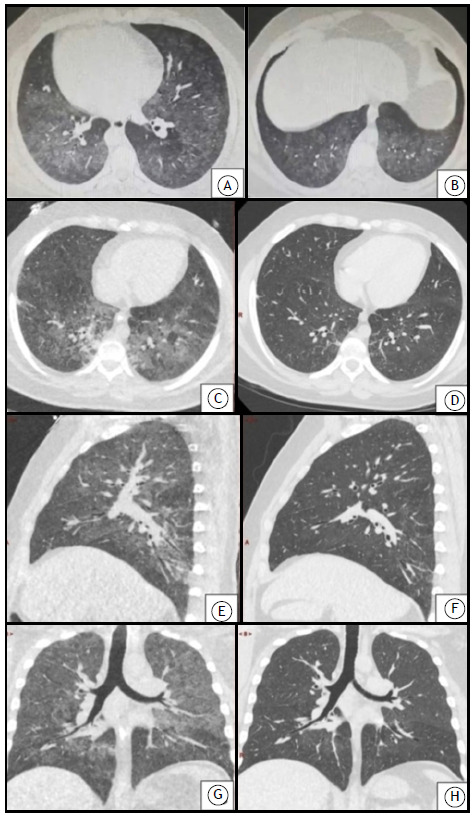

The hidden dangers of electronic cigarettes: e-cigarette, or vaping, product-use associated lung injury requiring extracorporeal membrane oxygenation.

电子烟的隐患:电子烟或电子烟与产品使用相关的肺损伤需要体外膜氧合。